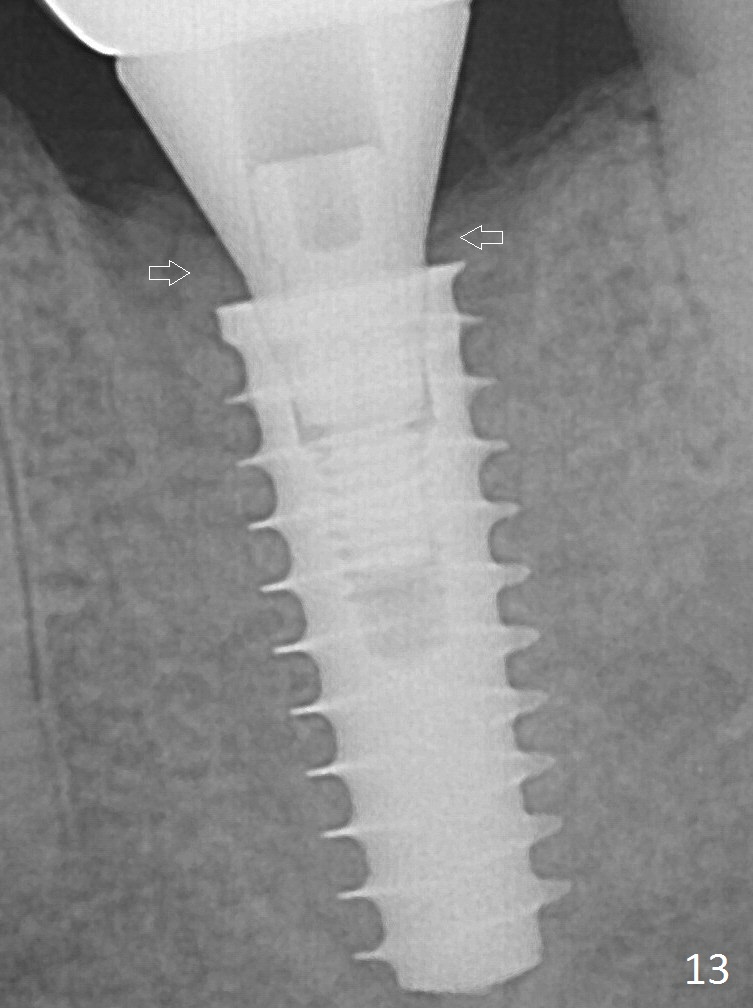

Insertion torque of a 5x13 mm implant is <20 Ncm (Fig.7). A 6.5x4(4) mm pair abutment is placed (A), apparently proper for restoration. Allograft is placed prior to immediate provisional. The patient complains of bad smell from the site 24 days postop. When the provisional is removed, the abutment is found to be mobile. When the latter is removed with local anesthesia, bone graft granules are attached to the socket above the lightly mobile implant. In fact the latter appears to be stable after a few turns by finger. A healing screw is placed; the socket is closed with collagen plug and 4-0 Chromic gut sutures. It appears that a larger implant should have been used to achieve higher torque. Two months later (3 months postop), the coronal end of the implant is partially exposed. A 5x4 mm healing abutment is placed. It appears that the implant is stable. The implant appears to have osteointegrated 4 months postop (Fig.11). Impression is taken. New bone has apparently covered the implant plateau 8 months postop (3 months post cementation (Fig.13 arrows)). The lower two-thirds of socket have disappeared.